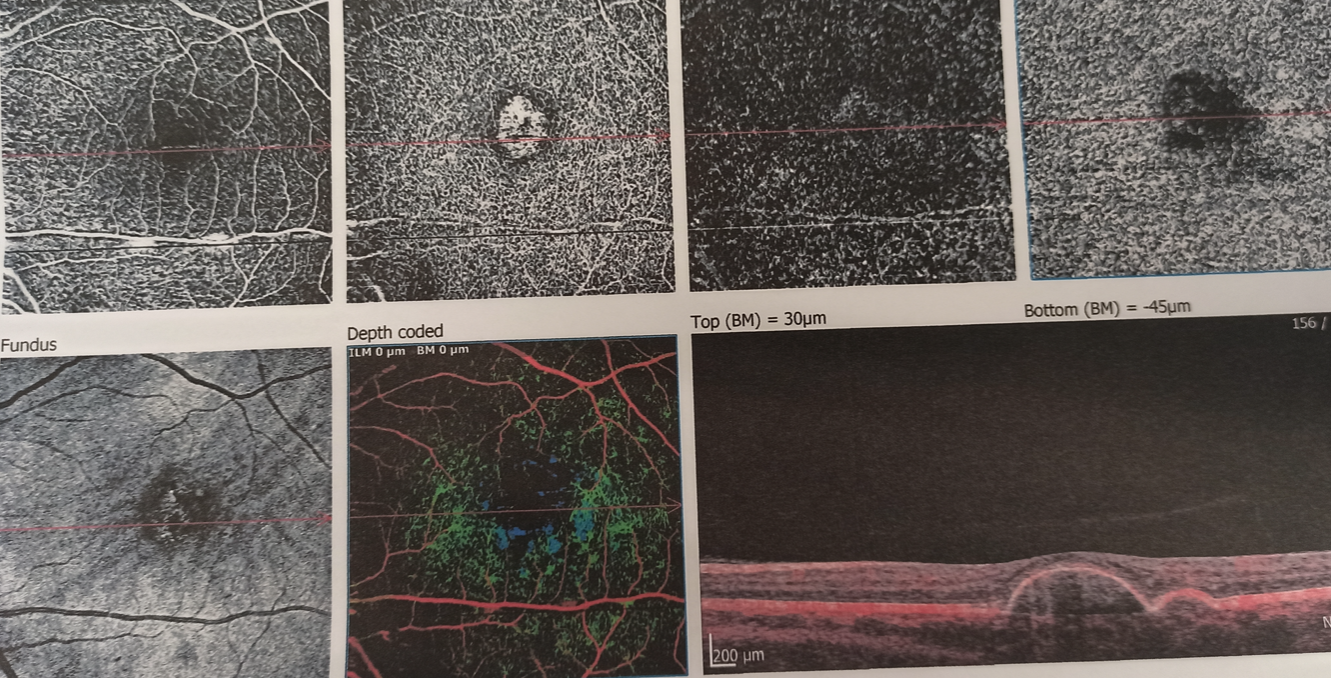

Об'єктивно - на правому оці субретинальний крововилив від аркади до аркади, з елементами субпігментного крововиливу, кров у стадії розсмоктування й у деяких ділянках фіброзування згустку.

На лівому оці друзеноїдне відшарування пігментного епітелію, ВМД (суха форма), тобто все ще попереду.

З урахування масивності крововиливу та загрози розвитку подібних станів в перспективі на парному оці, прийнято рішення дренувати субретинальний крововилив, а з урахуванням давності процесу зроблено припущення, що фібриноліз вже відбувається й в тканинних активаторах плазміногену (ТАП) потреби немає.

Під час операції вдалося відмити значну частину субретинальної крові, що дає право сподіватися на збереження макулярних функцій, разом з цим, згорток крові, що знаходився під сітківкою протягом 3 тижнів, вже почав фіброзуватися - такі тяжі видалити не вдалося. Ми розраховуємо на те, що такі тяжі розташовуються ближче до аркад, тому на фовеолярні функції впливати не повинні.